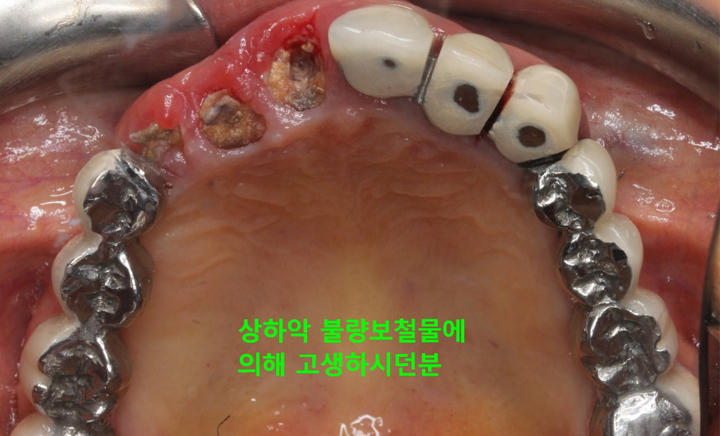

경제적인 비용 때문에 대부분은 틀니를 하게 됩니다.하지만 틀니를 해도 예전의 기능을 100% 회복하지는 못합니다. 완전 틀니의 경우 보통 10~30%의 기능만이 회복되며 잇몸 위에 얹어지는 구조물이므로 잇몸에 압박을 가하게 되며 이로 인해 잇몸이 부을 수도 있고 심하면 염증이 생기거나 상처가 생겨 곪을 수도 있습니다.

그리고 위턱의 틀니는 입천장이 있어 그나마 고정이 잘되지만 아래턱은 그런 구조물도 없는데다 혀가 자꾸 방해하기 때문에 고정하기가 쉽지 않아 틀니가 움직이는 불편함이 생깁니다. 이러한 틀니의 단점을 보완하고 틀니의 경제성과 임플란트의 기능성을 결합해 만들어진 것이 틀니 임플란트 입니다.